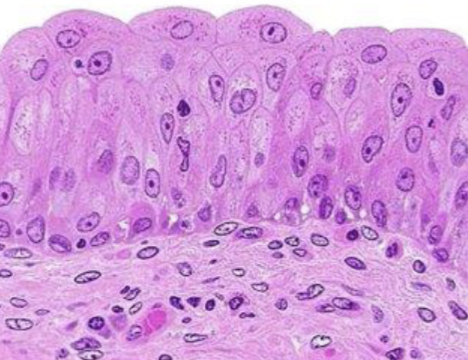

Clasifique tejido epitelial

urotelio

Indique sitio anatómico donde se encuentra

vejiga

Clasifique tejido epitelial

estratificado queratinizado

Indique sitio anatómico donde se encuentra

piel delgada

Forma de sus células

plano

Número de capas

estratificado

Indique función

protección